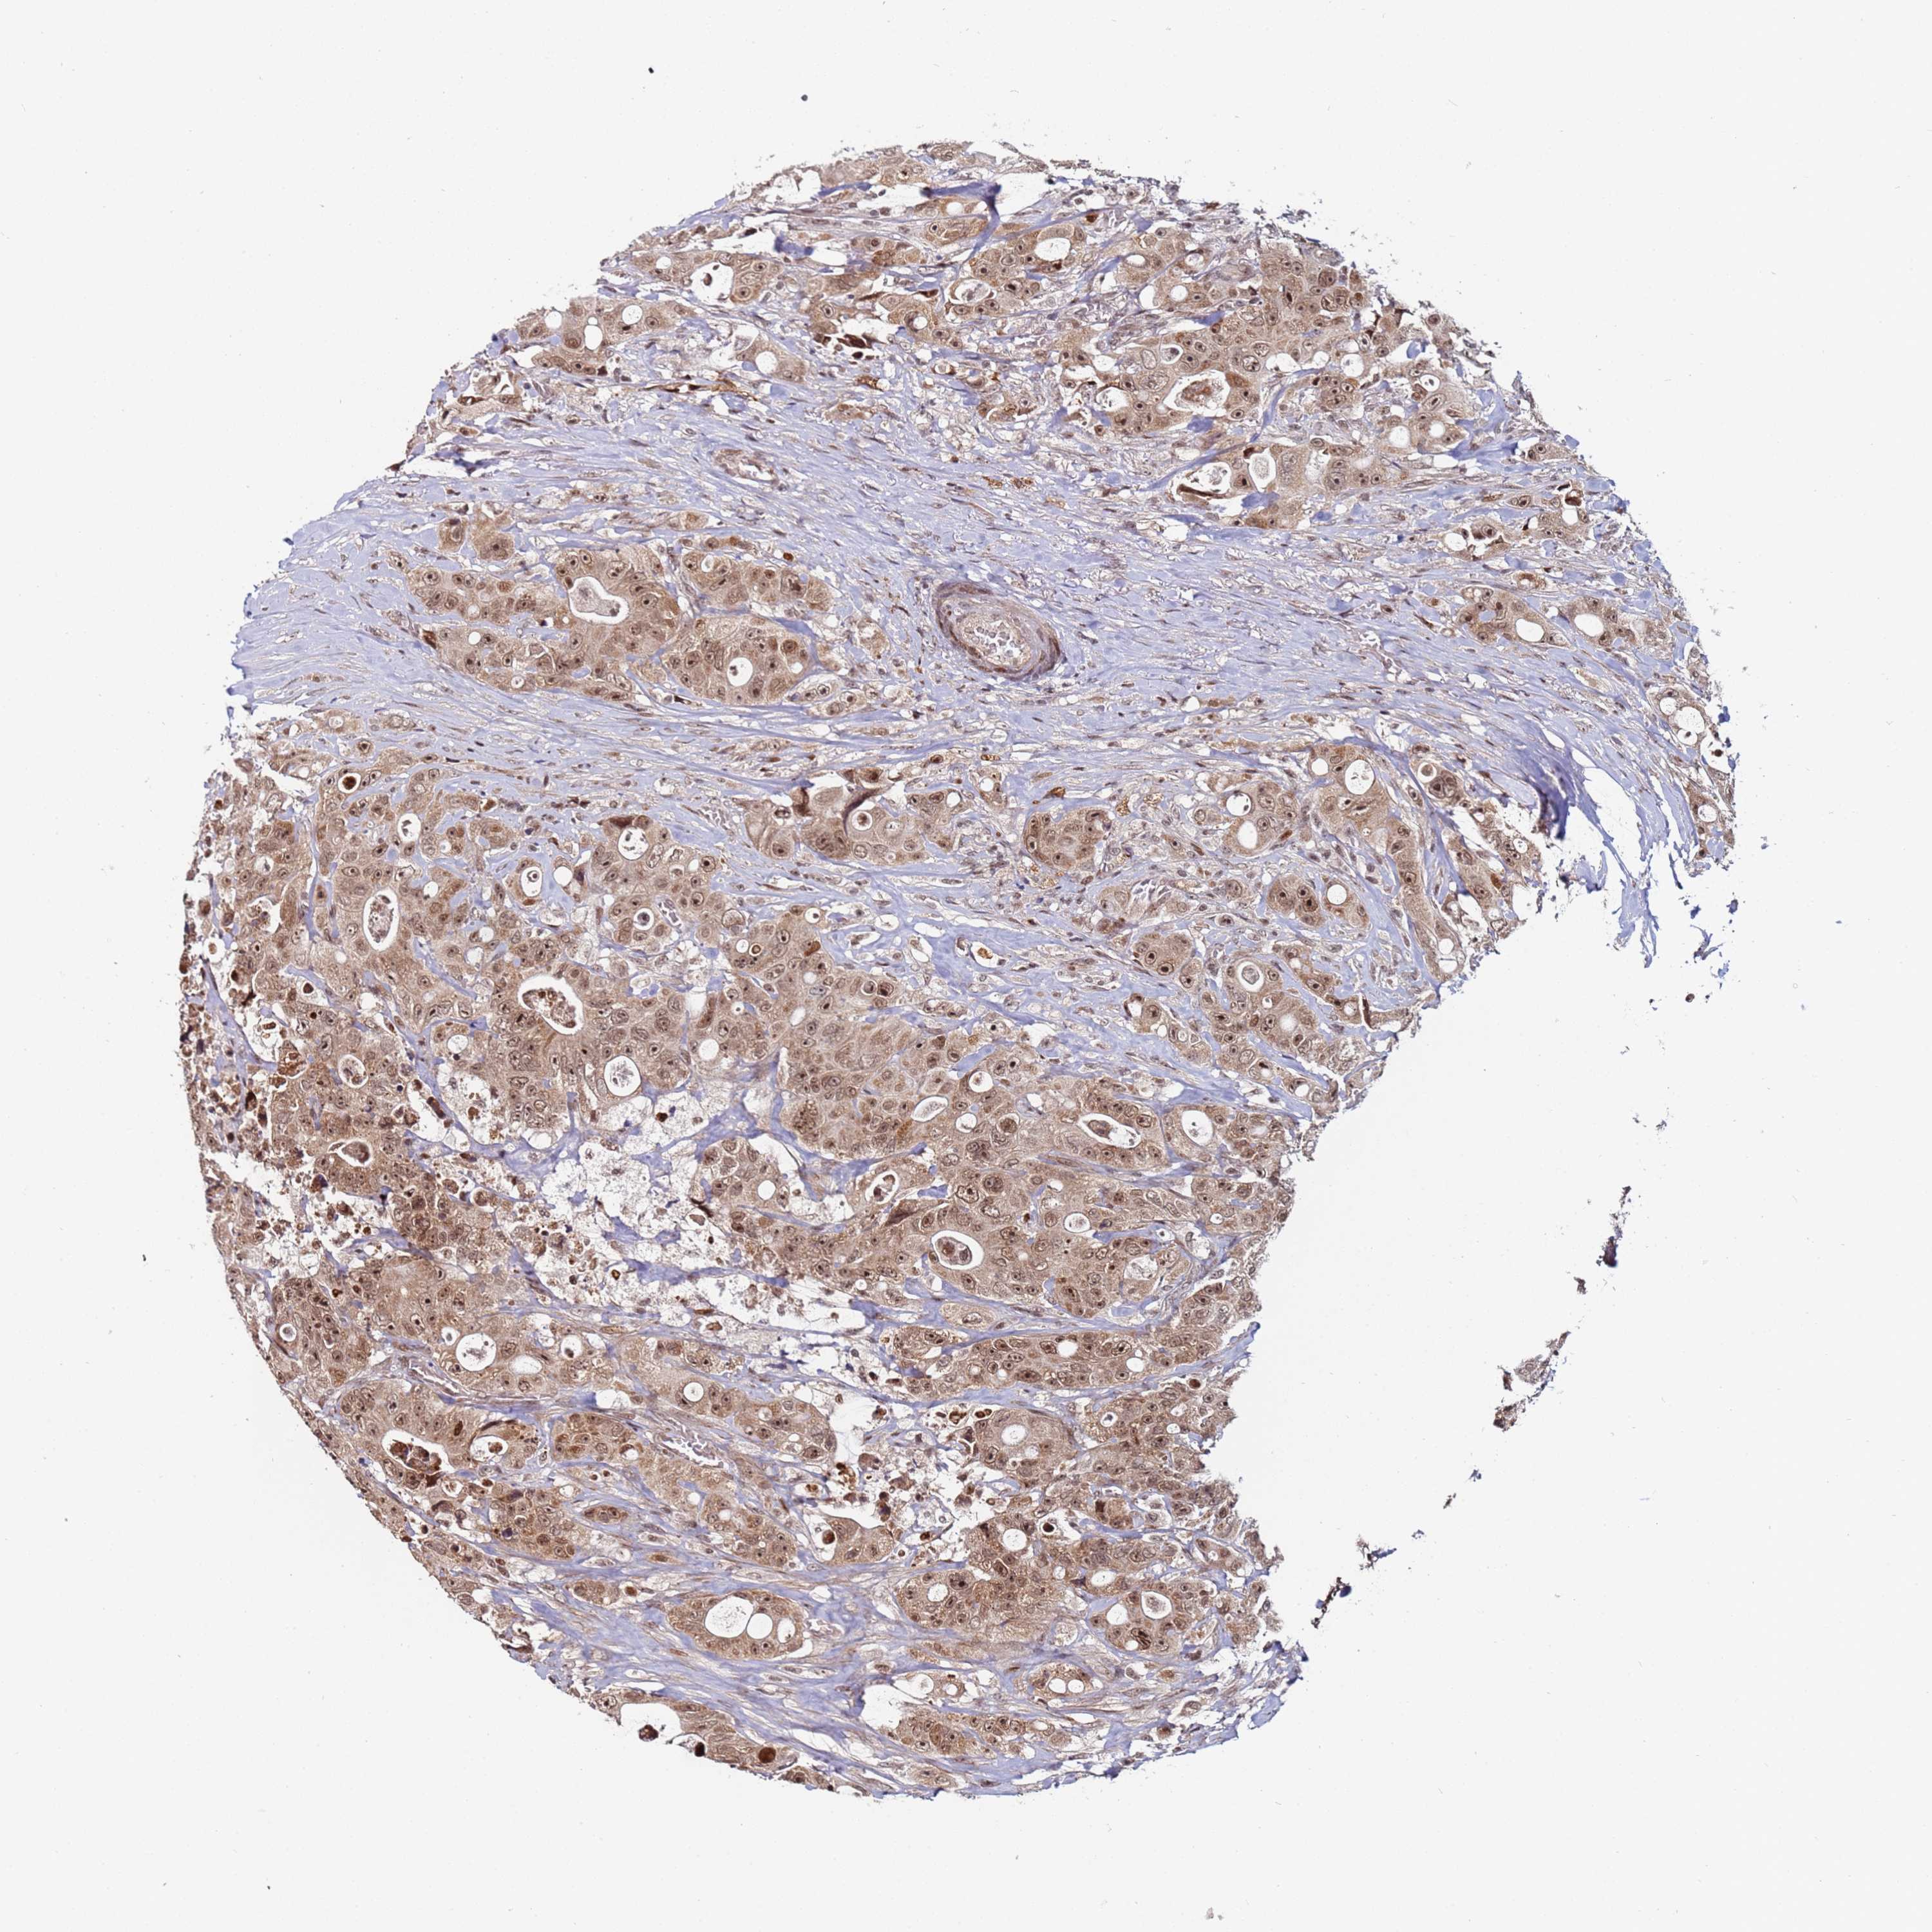

CANCER COLORECTAL CANCER Show tissue menu

Colorectal cancer

Human cancer

Colon adenocarcinoma